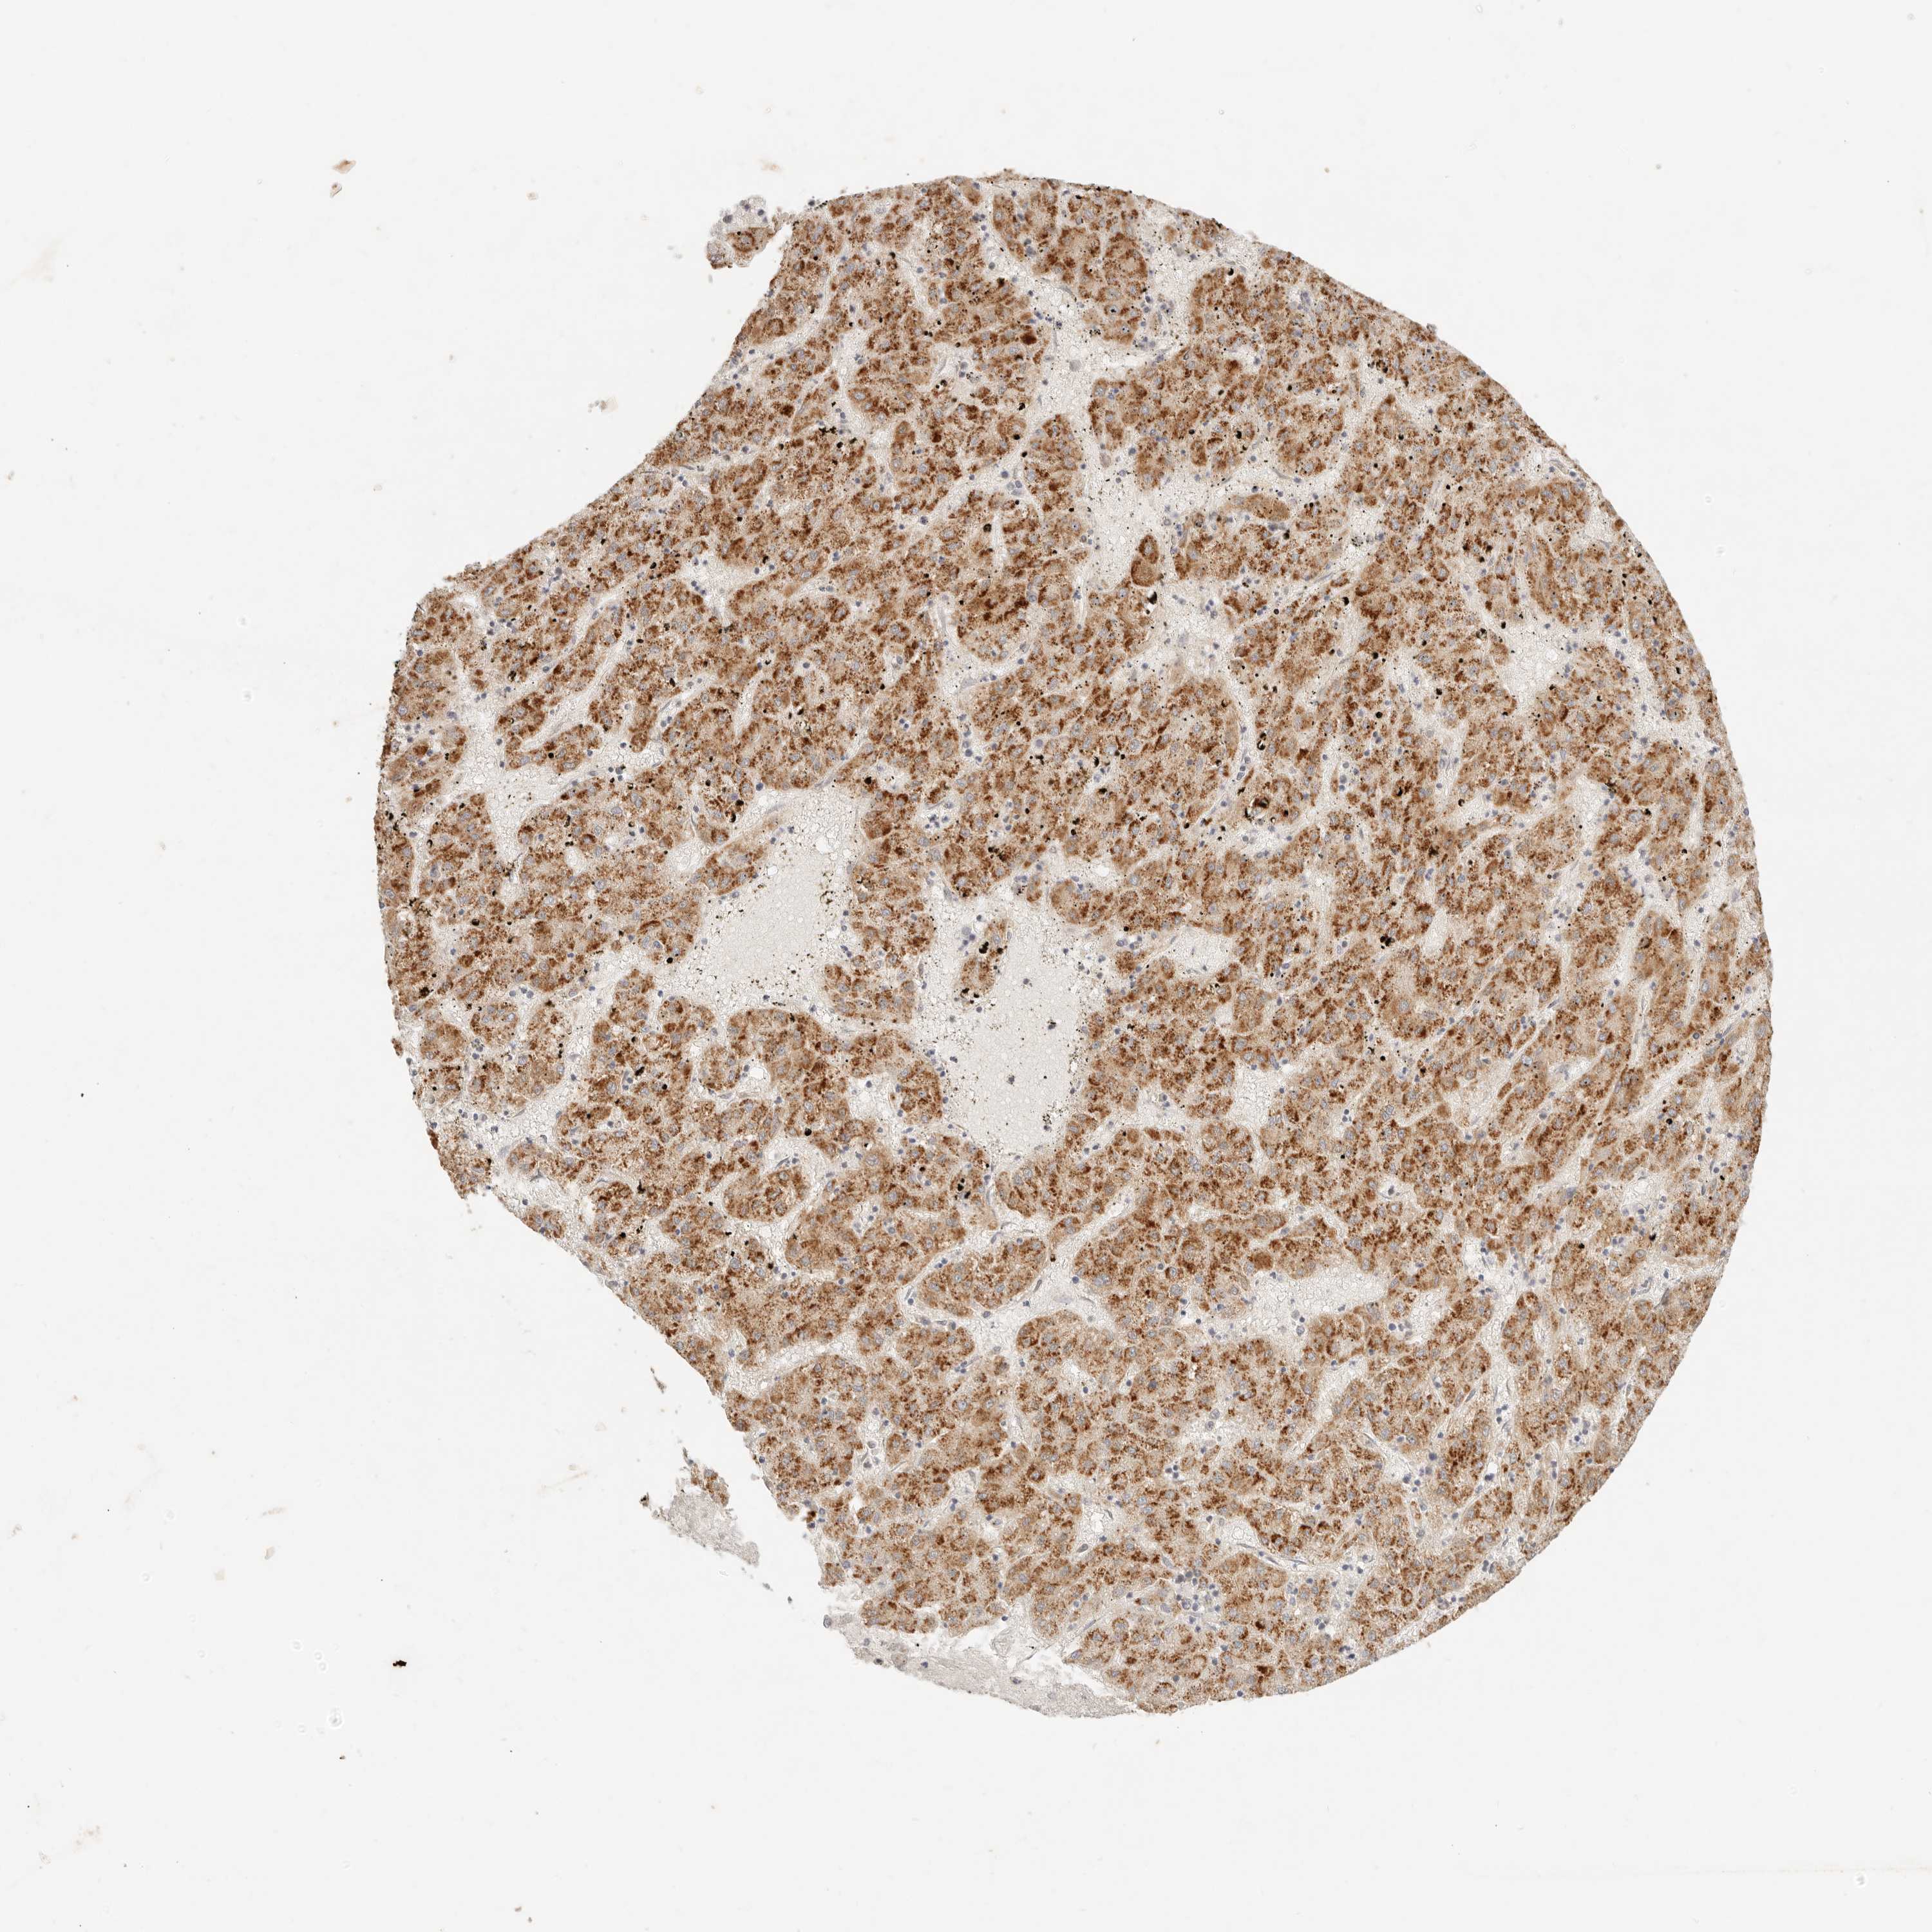

LIVER CANCER - Protein expressioni

A mouse-over function shows sample information and annotation data. Click on an image to view it in a full screen mode. Samples can be filtered based on level of antibody staining by selecting one or several of the following categories: high, medium, low and not detected. The assay and annotation is described here.

Note that samples used for immunohistochemistry by the Human Protein Atlas do not correspond to samples in the TCGA dataset.

Antibody stainingi

Antibody staining in the annotated cell types in the current human tissue is reported as not detected, low, medium, or high, based on conventional immunohistochemistry profiling in selected tissues. This score is based on the combination of the staining intensity and fraction of stained cells.

Each image is clickable and will lead to virtual microscopy that enables deeper exploration of all samples and also displays staining intensity scores, fraction scores and subcellular localization as well as patient and tissue information for each sample.

Antibody HPA021192

Antibody HPA021195

Antibody HPA028759

Antibody CAB021094

Staining

High

Medium

Low

Not detected

Location

Nuclear

Cytoplasmic/membranous

Cytoplasmic/membranous,nuclear

Cholangiocarcinoma

Carcinoma, Hepatocellular, NOS